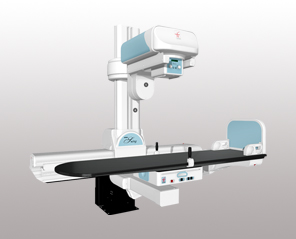

کمپانی General Medical Merate S.p.A. یا همان GMM فعالیت خود را از سال ۱۹۵۲ آغاز کرده و در حال حاضر، یک هلدینگ مطرح در جهان است. تولیدات این کمپانی ایتالیایی شامل دستگاه فلوروسکوپی، رادیولوژی دیجیتال، ماموگرافی دیجیتال، ایکسری پرتابل، C-arm و تخت جراحی C-arm است. برخی برندهای مطرح مانند MT-MEDICAL TECHNOLOGY، MECALL، MERATE POWER، PRIMAX، D/VISION LAB و IMS GIOTTO زیر مجموعه این هلدینگ هستند.

همکاری گروه تجهیزات پزشکی رئوف با این کمپانی، از سال ۱۳۹۲ آغاز شد و ما نیز در راستای تحقق این اهداف در مرزهای خود کوشیدهایم و خرسندیم که تا به امروز، با نصب دستگاههای رادیولوژی و ماموگرافی GMM، بسیاری از مراکز درمانی را با سیستم پیشرفته این دستگاهها تجهیز کردهایم.